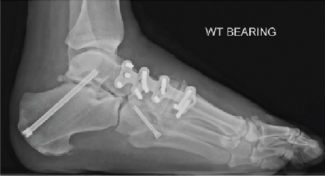

The concept of medial column fixation in Charcot foot utilizes the strength of the multiple screw fixation points and spanning to areas of stronger bone to stabilize the medial column. In our experience, this form of fixation has demonstrated...